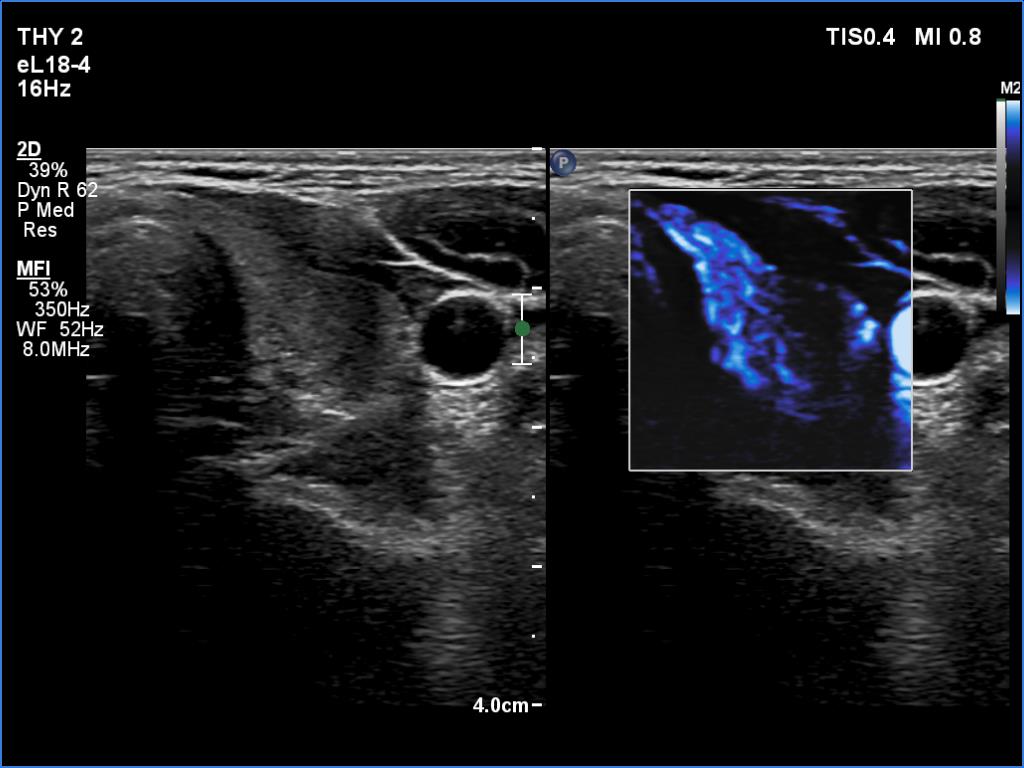

Case 1348

Examination a year after the first visit (ultrasonographic picture 8)

Left lobe, transvrse scan, microflow imaging. According to the hypoechoic lateral part, the vascularity remained absent.